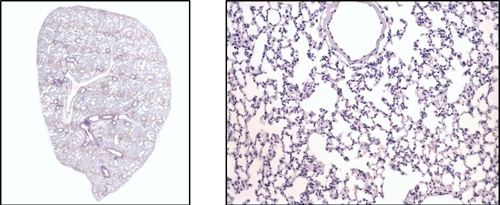

Pulmonary fibrosis is a severe progressive pathological condition in many respiratory diseases. Idiopathic pulmonary fibrosis (IPF) is the most common with high morbidity and mortality. There is currently no cure and the two most commonly used drugs for treatment simply reduce progression but do not result in regression. Axis Bio offer the bleomycin-induced lung fibrosis model in both mice and rats to study efficacy in both acute or chronic disease.

Non induced